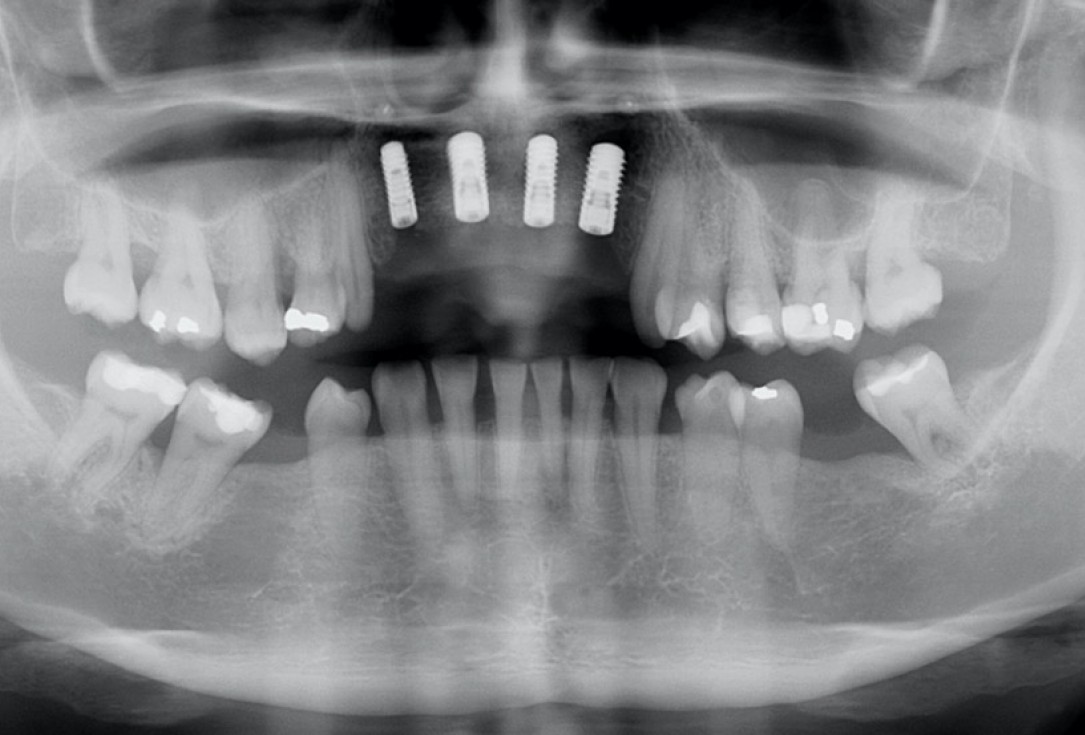

4/17 - X-ray scan after extraction of failing implantsRestoration of all four incisors with maxgraft® bonebuilder - Dr. Dr. Dr. O. Blume